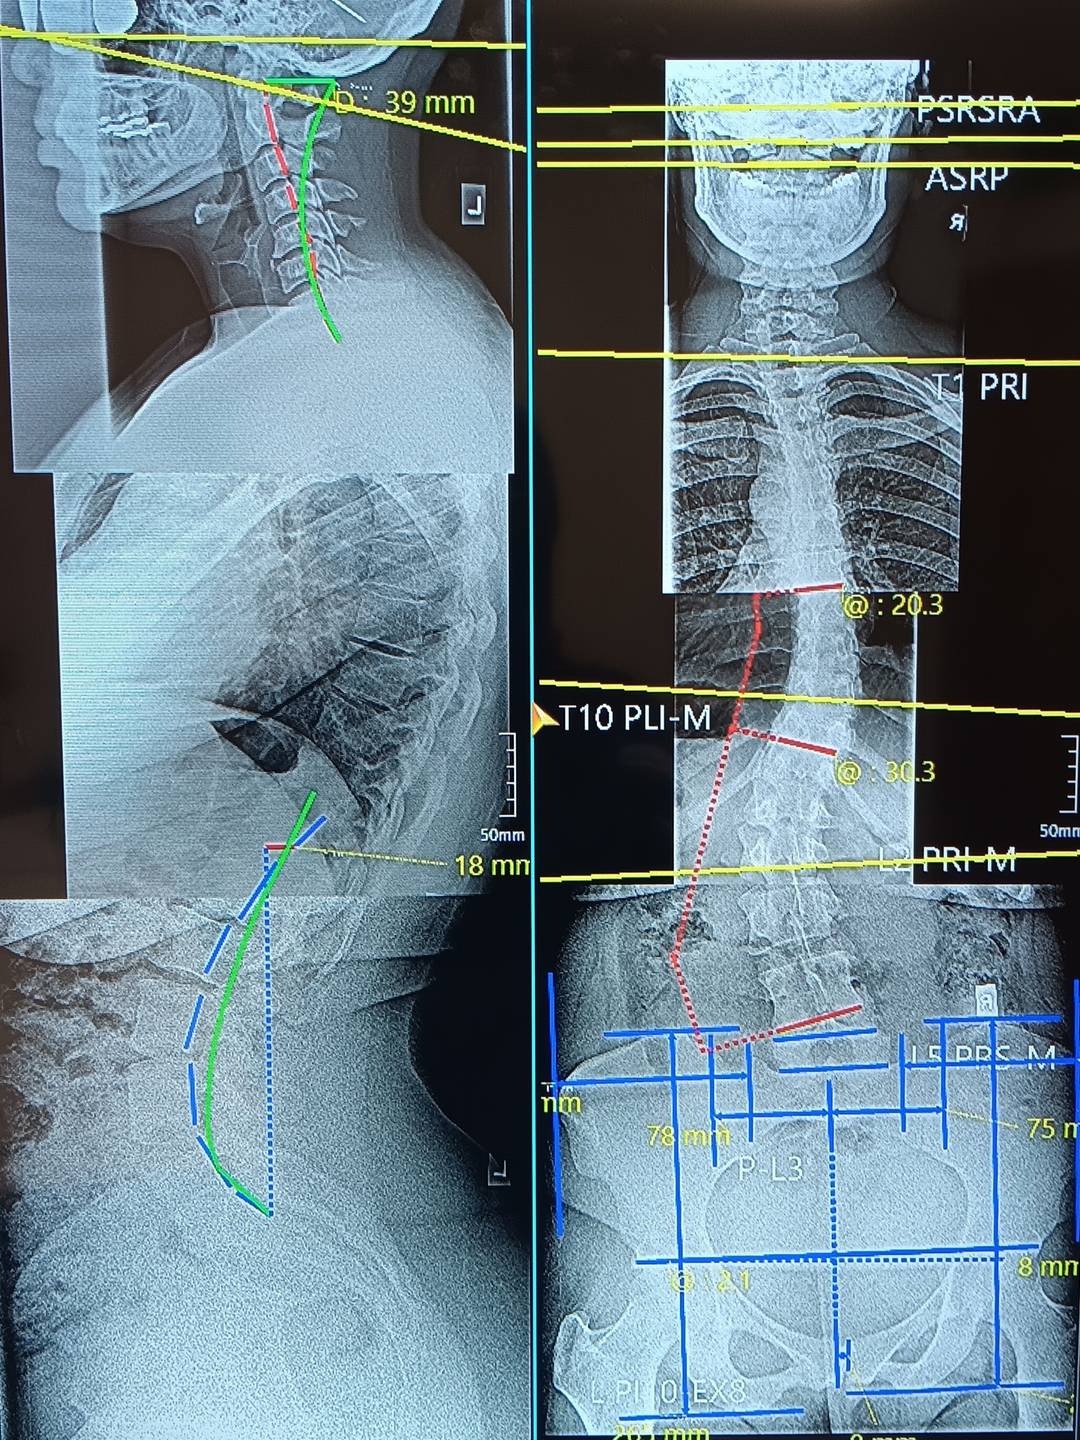

On the left you'll see a healthy spine and on the right is my spine. My spine is clearly doing way too much. It's been like this since at least adolescence. I went to the doctor when I was 19 and they tested a lump on my side for cancer. It wasn't cancer. I asked that they keep testing to find out what it was. They told me it was fat. I asked why it was only on on side. Doctor shrugged and sent me home. One x-ray could have saved me over 20 years of pain and suffering. I'm too tired to be angry. I just want to get well.

There were only a few symptoms that I could not address through sound, medicinal herbs, exercise, and other diet and lifestyle changes. Menstrual cramps because my pelvis is tilted to the left and a pain in my left shoulder because the top of my spine is curving forward. This is how I ended up at the chiropractor around one month before my 43rd birthday and learned that I had scoliosis. I am a few weeks into treatment and already experiencing relief including NO MENSTRUAL CRAMPS!!!!